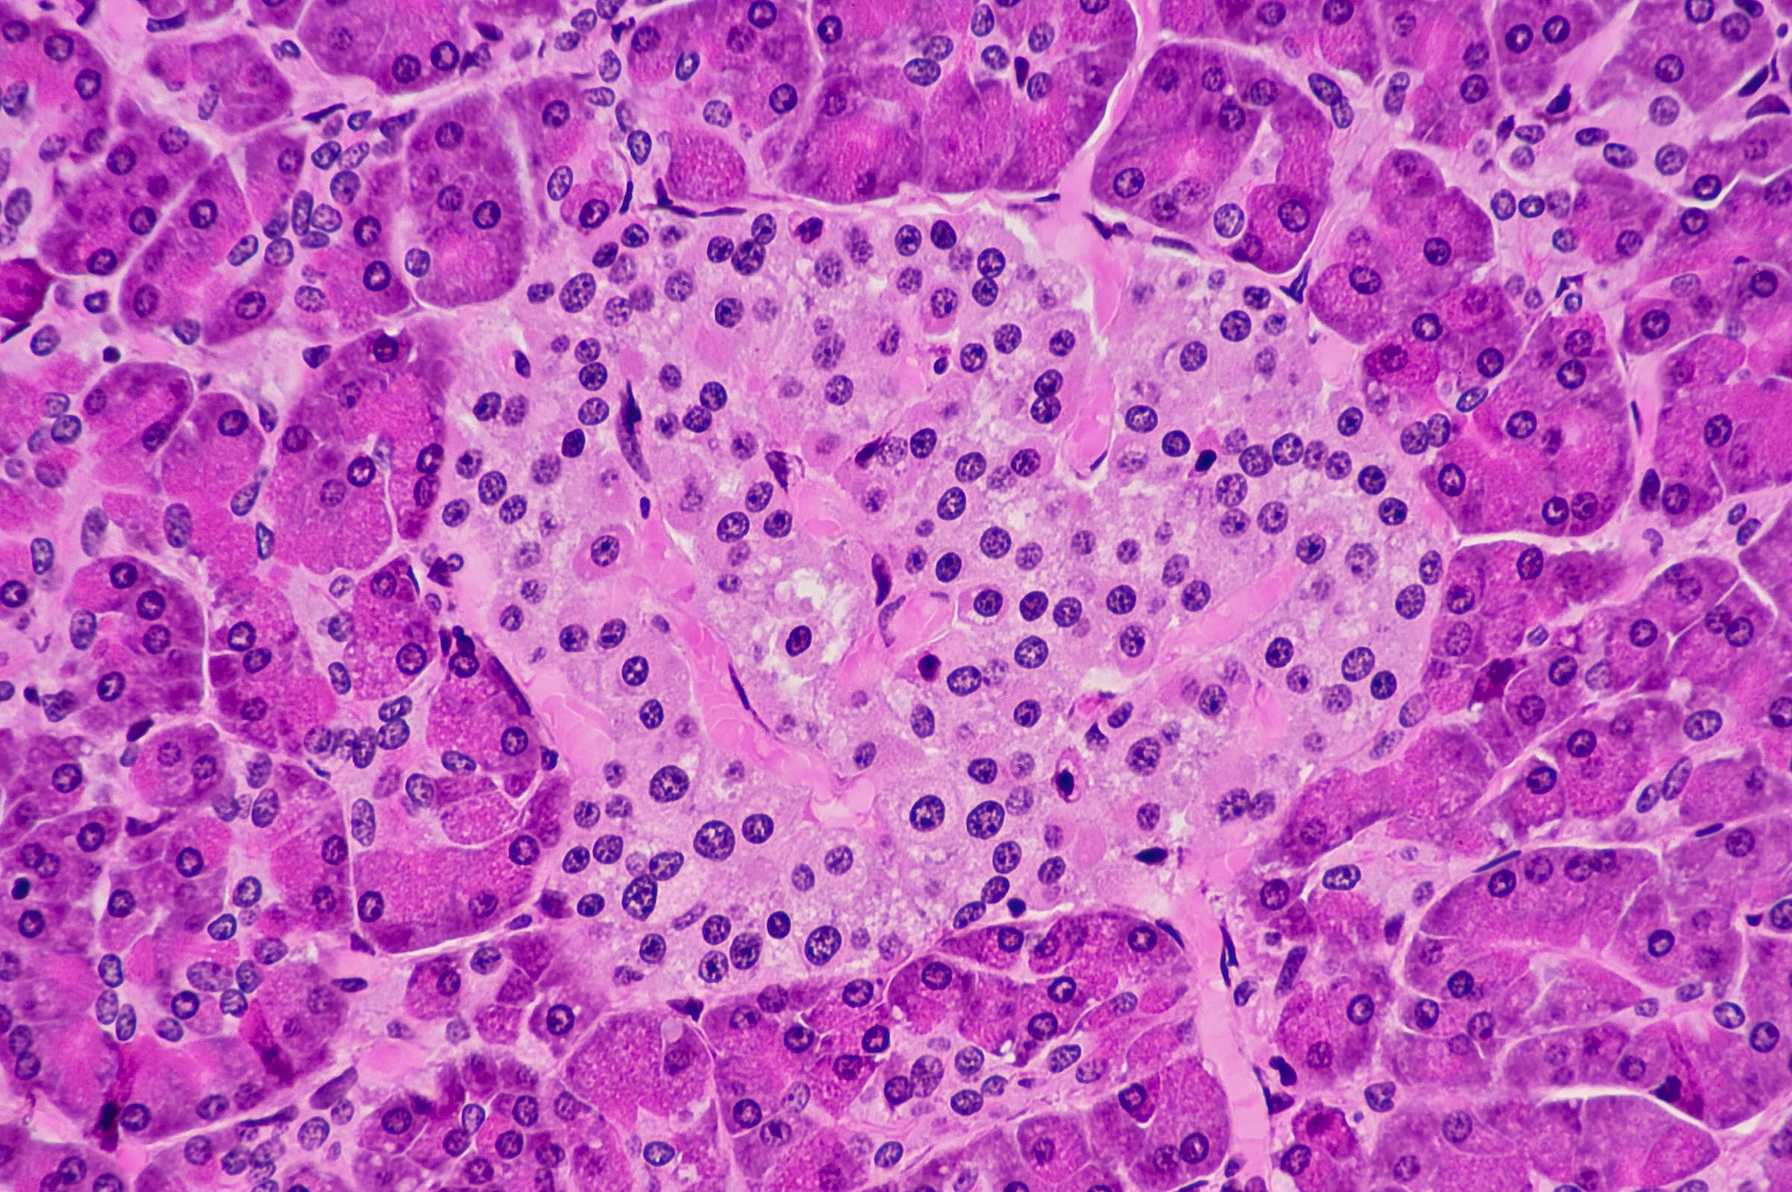

- The pathophysiology, diagnosis and treatment of disorders of endocrinology, diabetes and metabolism

- Multidisciplinary management of complex thyroid, pituitary and neuroendocrine tumors

The Michael F. Price Center for Genetic and Translational Medicine and Harold and Muriel Block Research Pavilion is a medical research facility that houses 40 state-of-the-art laboratories, research support facilities and a 100-seat auditorium. The research taking place here is at the frontier of biomedical science, and has the potential to impact every area of medicine, including cardiovascular disease, genetic disorders, cancer, diabetes, Alzheimer’s disease and others. With a focus on genetic medicine, researchers use their laboratory findings to develop medical advances that will benefit the Bronx, New York City and, ultimately, the entire world.

Researchers from Albert Einstein College of Medicine secured $178 million from the National Institutes of Health (NIH) in 2019, with $14.7 million in funding granted to researchers in the Division of Endocrinology, Diabetes and Metabolism. The Division carries out ongoing clinical, basic science, translational and behavioral research in a range of endocrine science areas, including diabetes and aging research, along with emerging opportunities in thyroid, metabolic bone disease and neuroendocrine research.

Our NIH-funded research centers include the Einstein Sinai Diabetes Research Center, home to more than 120 faculty laboratories conducting basic, translational and clinical research in diabetes, obesity and metabolism; the New York Regional Center for Diabetes Translation Research, specializing in bio-psychosocial and behavioral research, with a focus on the social determinants of health; the Institute for Aging Research and Nathan Shock Center of Excellence in the Basic Biology of Aging, which conducts basic, translational and clinical research; and the Global Diabetes Institute, which establishes strategic global partnerships for research on lean diabetes and improving diabetes education.